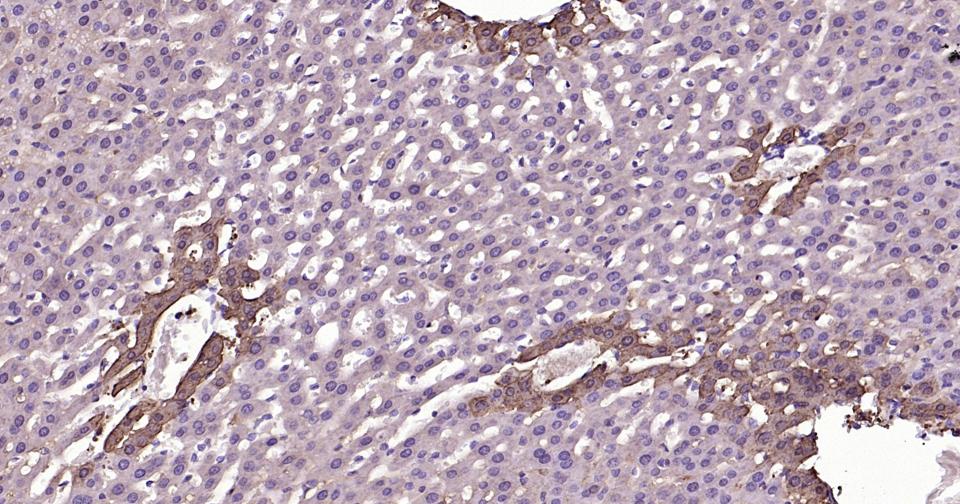

Paraformaldehyde-fixed, paraffin embedded Human Glioma; Antigen retrieval by boiling in sodium citrate buffer (pH6.0) for 15 min; Antibody incubation with Glutamine synthetase Monoclonal Antibody, Unconjugated(bsm-61160R) at 1:200 overnight at 4°C, followed by conjugation to the SP Kit (Rabbit, SP-0023)and DAB (C-0010) staining.